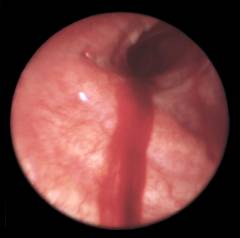

Фото бронхоскопии, как выглядят больные бронхи?

Так выглядят здоровые бронхи во время бронхоскопии.

Эти изменения характерны для туберкулеза бронха.